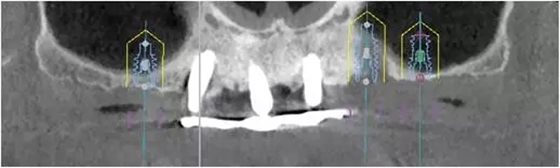

2、增加上頜種植體數(shù)量,分別與16、25、26植入3顆,行6顆種植體支撐的常規(guī)種植固定義齒修復(fù)(圖7)。16、25、26區(qū)剩余骨高度嚴(yán)重不足是該方案的不利方面,存在因需要上頜竇底提升手術(shù)所帶來(lái)的相應(yīng)手術(shù)風(fēng)險(xiǎn)。但是,上頜竇底提升術(shù)是一個(gè)成熟、可靠的技術(shù)方法,經(jīng)過(guò)與患者充分溝通,最終選擇了這一方案。

1、開(kāi)窗法雙側(cè)上頜竇底提升術(shù),聯(lián)合25區(qū)植骨術(shù);

2、6個(gè)月后延期種植,分別與16、25、26植入3顆種植體(如圖7所示);